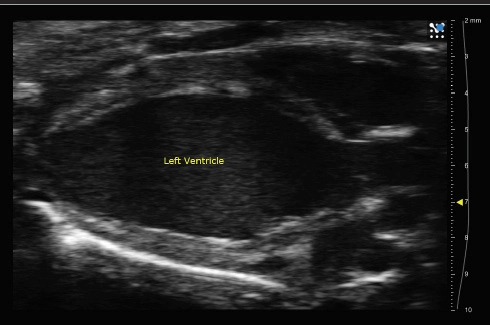

Cardiology

Perform basic cardiovascular research with small animal models including functional and anatomical analyses.